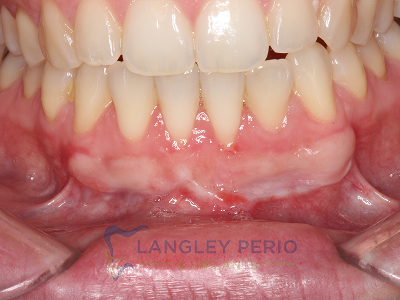

Case 1

Connective tissue grafting was performed to correct gingival clefting caused by over-aggressive toothbrushing